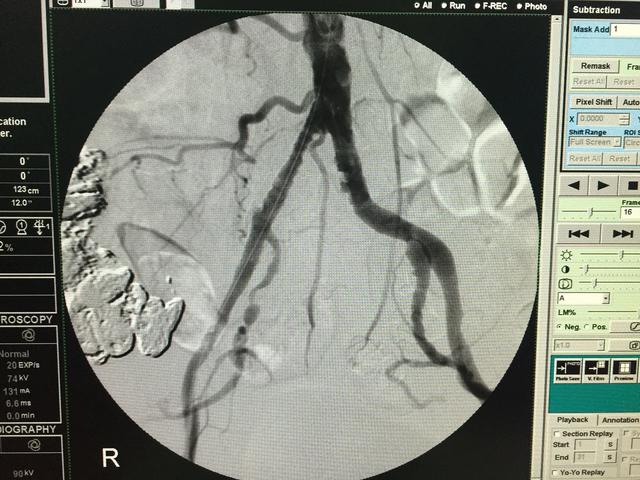

血管外科经常收治一些病人是因为“肾虚”而来的,他们的主要表现是:腰酸腿痛、下肢发凉伴乏力、臀部麻木、性功能障碍等等。这些表现显然符合中医的肾虚,在临床上更容易与腰椎病、偏瘫、髂关节及膝关节病鉴别不清,由于血管病变多见于中老年,与上述疾病发病年龄相当,而且往往会同时伴发,导致长期误诊。

对于这些患者,尤其是孤立的下半身症状患者,一定要注意下肢股动脉、腘动脉、足背及胫后动脉搏动的情况。其次注意温度、皮毛脱落、肌肉萎缩等,另外,还要注意与运动的关系,血管病变类似于心绞痛,活动后出现困痛。

血管外科经常收治一些病人是因为“肾虚”而来的,他们的主要表现是:腰酸腿痛、下肢发凉伴乏力、臀部麻木、性功能障碍等等。这些表现显然符合中医的肾虚,在临床上更容易与腰椎病、偏瘫、髂关节及膝关节病鉴别不清,由于血管病变多见于中老年,与上述疾病发病年龄相当,而且往往会同时伴发,导致长期误诊。

对于这些患者,尤其是孤立的下半身症状患者,一定要注意下肢股动脉、腘动脉、足背及胫后动脉搏动的情况。其次注意温度、皮毛脱落、肌肉萎缩等,另外,还要注意与运动的关系,血管病变类似于心绞痛,活动后出现困痛。